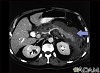

The following imaging tests that can show swelling of the pancreas may be done, but are not always needed to make a diagnosis of acute pancreatitis: